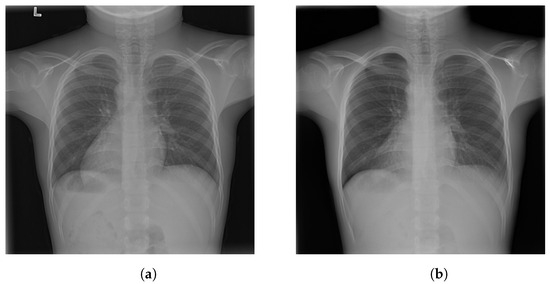

4.1. -LDP-Processed CXR Images

4.2. Qualitative Assessment of LDP-Processed CXR Images